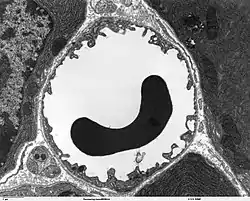

![]() Microcirculation in the capillary | |

The microcirculation is the circulation of the blood in the smallest blood vessels, the microvessels of the microvasculature present within organ tissues.[1] The microvessels include terminal arterioles, metarterioles, capillaries, and venules. Arterioles carry oxygenated blood to the capillaries, and blood flows out of the capillaries through venules into veins.

The vessels on the arterial side of the microcirculation are called the arterioles, which are well innervated, are surrounded by smooth muscle cells, and are 10-50 μm in diameter.[2] Arterioles carry the blood to the capillaries, which are not innervated, have no smooth muscle, and are about 5-8 μm in diameter. Blood flows out of the capillaries into the venules, which have little smooth muscle and are 10-200 μm. The blood flows from the venules into the veins. Metarterioles connect arterioles and capillaries. A tributary to the venules is known as a thoroughfare channel.